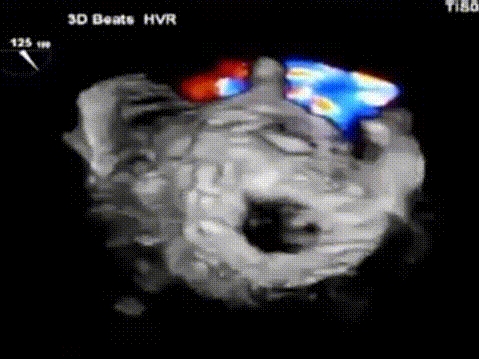

术前,陈茂教授带领团队基于详尽的CT评估测量,判断评估患者术中风险并选择适合的手术策略。通过CT影像分割三维二尖瓣瓣环、测量其径线、计算二维投影径线并模拟植入HighLife TSMVR瓣膜,判断人工瓣膜与毗邻组织贴靠位置良好且无左室流出道梗阻风险。但该例患者二尖瓣装置结构较为特殊,存在风湿性病变所致腱索增粗、短缩、融合,为导丝成环步骤带来挑战,术中输送器需要始终保持合适深度,且导丝成环过程中需始终保持高位(靠近二尖瓣环底部位置)环绕腱索形成通路,以避免植入固定环时位置靠下导致瓣膜释放时移位。

手术采用左侧股动脉入路与右侧股静脉入路,由股动脉入路将环形放置导管送至术前评估深度,在高位开始导丝成环步骤。多学科团队紧密协作,在术前规划的DSA投射体位和梁玉佳、魏薪医师的超声引导配合下,术者精细操控,导丝顺利按预期路径环绕腱索,仔细评估完成导丝成环这一关键的手术步骤,过程顺利,建立固定环植入的重要轨道。